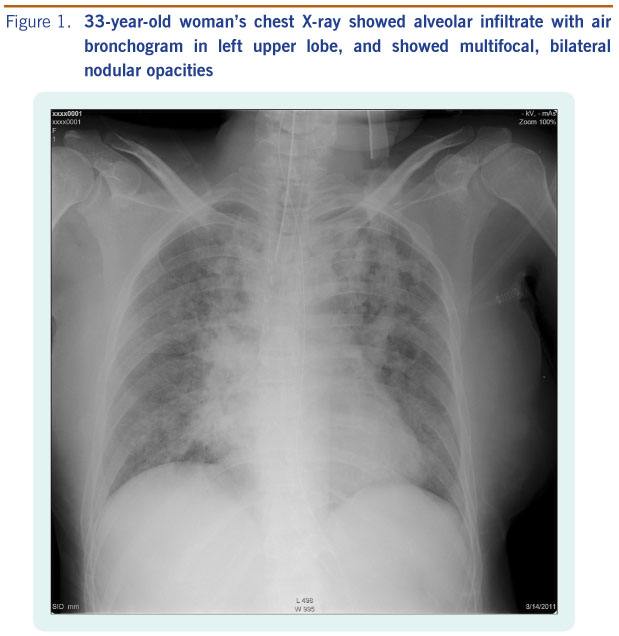

Hình 1